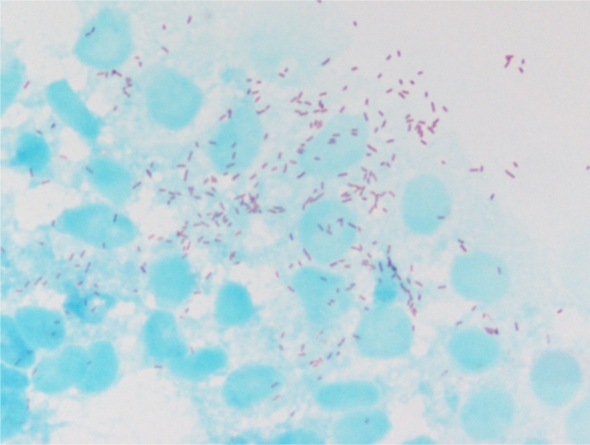

De forma general, las babesias infectan a los eritrocitos (glóbulos rojos) y producen anemia hemolítica. El cuadro puede ser subclínico o, por el contrario, hiperagudo, agudo o crónico.

El diagnóstico se puede hacer mediante frotis directo de la sangre al microscopio, donde observaremos las babesias dentro de los glóbulos rojos, también en un análisis serológico tras dos semanas postinfección, e incluso por pruebas específicas de PCR para diagnosticar cuadros crónicos.